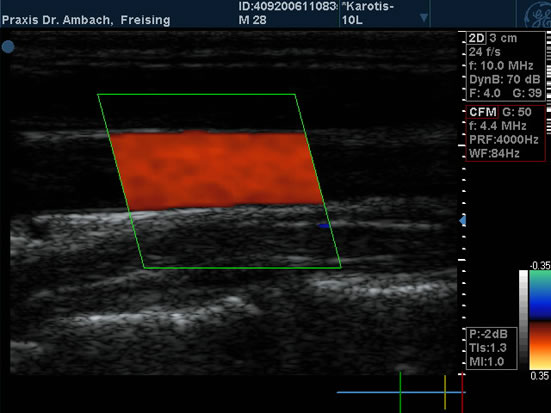

Gefäßdoppler

Gefäßdoppler - 1